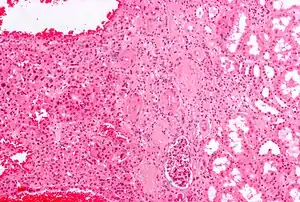

Micrograph of chromophobe RCC oncocytic variant, the main differential diagnosis of renal oncocytoma.

The main differential diagnosis of renal oncocytoma is chromophobe renal cell carcinoma oncocytic variant, which like the renal oncocytoma has eosinophilic cytoplasm, but has perinuclear clearing and, typically, some degree of nuclear atypia.